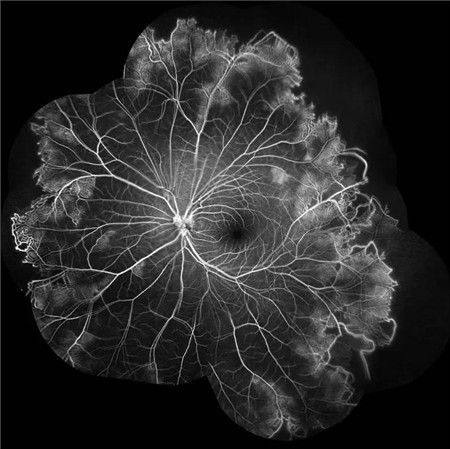

北京希玛眼科医院:IRVAN综合征引起的黄斑裂孔(案例分享)

经过详细的眼底检查后,患者被诊断为IRVAN综合征引起的右眼黄斑裂孔,张风院长带领医生团队为患者施局右眼玻璃体切除+剥膜+眼内光凝+气液交换手术,经过半个月的恢复,患者右眼术后视力由术前0.3-达到0.6-的状态,且裂孔呈逐渐闭合状态。